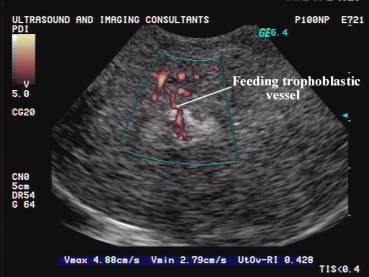

- Ультразвуковое исследование (УЗИ);